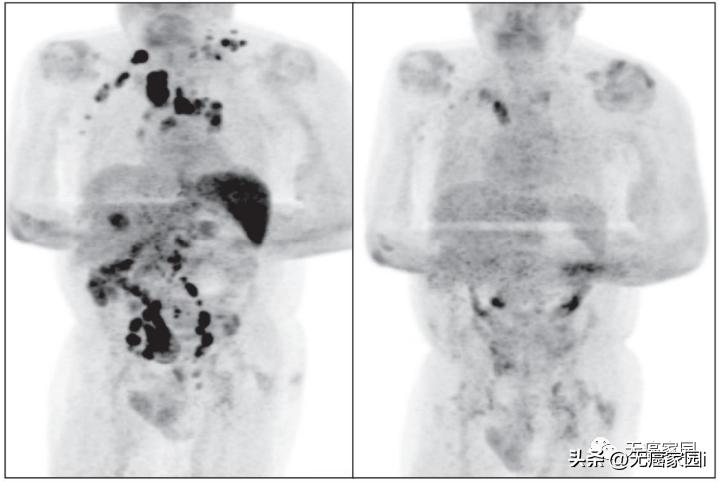

虽然期间有轻微的CAR-T疗法副作用,但神奇的是,短短的30天内,她的肿瘤完全消失。在附加的图像中显示了巨大的变化,左侧是取回CAR-T细胞前1周的扫描,右侧是1个月后的扫描。

2020年7月,阿达米进行了为期2年的CAR-T PET扫描,并完全缓解!现年61岁的她感觉自己挑战了人生的巨大困难,并打算对珠穆朗玛峰的攀登发起挑战!